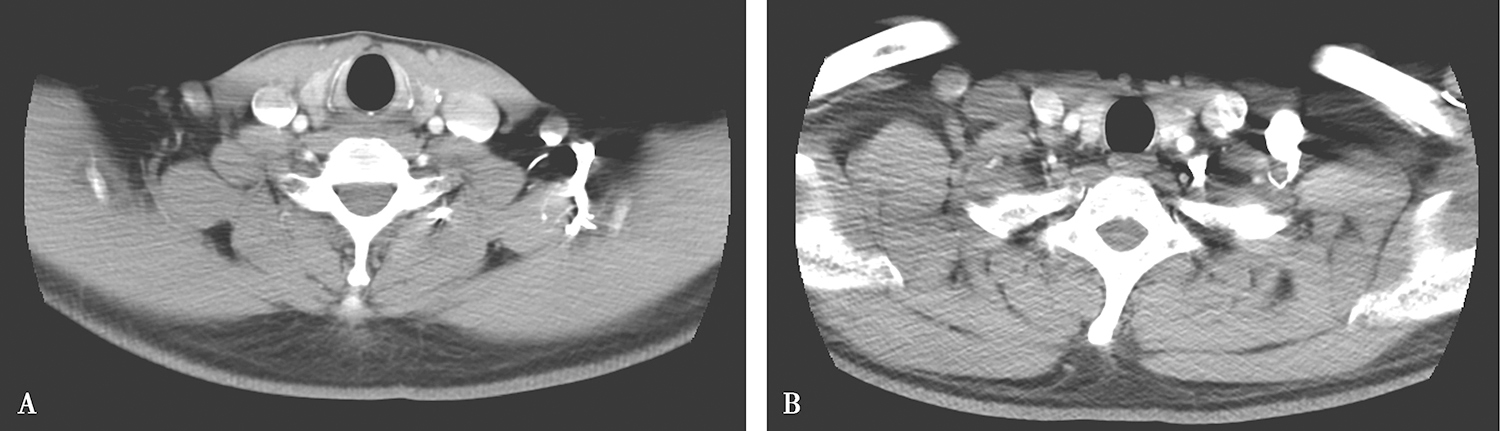

甲状腺右叶上极可见实性小结节,大小约0.8cm×0.6cm,强化较明显、不均,边界欠清楚(图2A);余甲状腺未见明确异常。右侧颈深链、锁骨上可见多发肿大淋巴结,大者短径约1.6cm,部分强化较明显(图2B);左颈部、锁骨上未见明确肿大淋巴结。

图2 颈部增强CT

A.甲状腺右叶上极实性小结节;B.右侧颈深链、锁骨上多发肿大淋巴结

影像学诊断:

(1)甲状腺右叶上极实性小结节,需警惕恶性,请结合超声及穿刺活检诊断。

(2)右侧颈深链、锁骨上多发淋巴结转移。